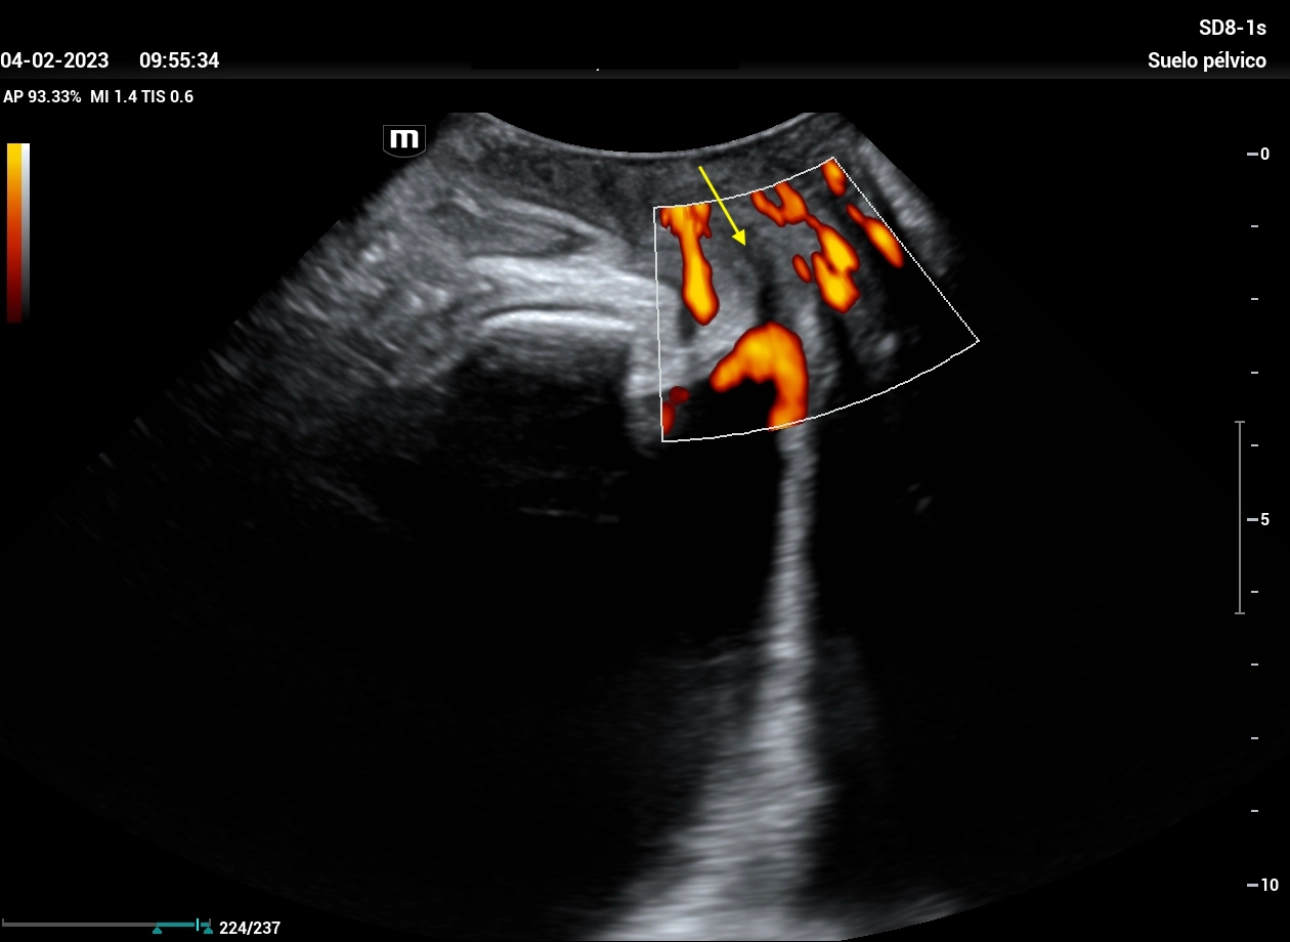

stress-urine-fig8

Figure 8: when placing color Doppler before the Valsalva maneuver, it is observed how the urethra fills with color (yellow arrow), which infers the passage of urine due to internal sphincter incontinence.